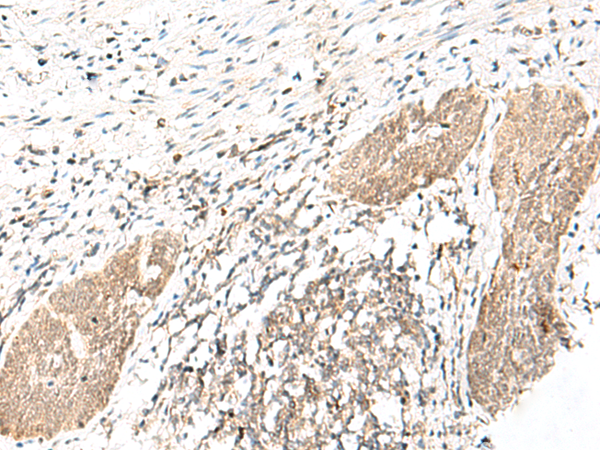

分类: 科研抗体货号: P02870别名: TASSC; HSPC299; NIPSNAP4应用: IHC反应种属: Human